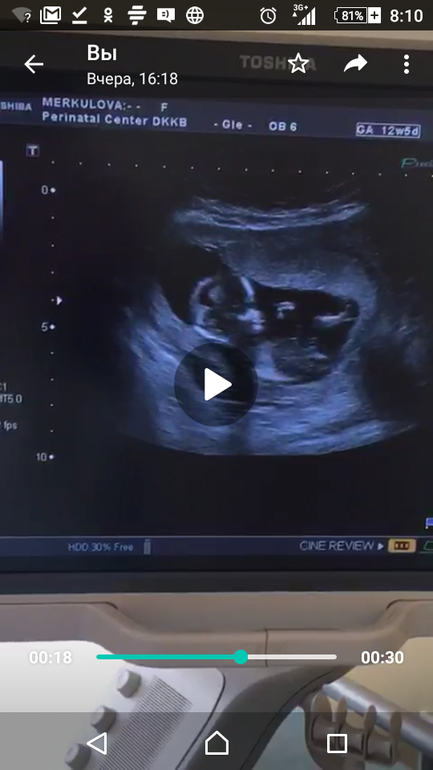

Фото со скрининга? Пол.

вроде выбрала кадры из видео, на которых что-то видно. Узист вчера сказала, что с большой вероятностью девочка. Срок 12,5 нед. Как думаете это действительно барышня?

По-моему, на фото 00:24 четко видно, что ДА. На остальных я не увидела, ноя плохо понимаю по нечетким картинкам УЗИ. Поздравляю Вас с доченькой.

нам с таким бугорком сказали что девочка☺ очень похоже)))

у нас вот так торчало)

а вот лобик на мальчика))